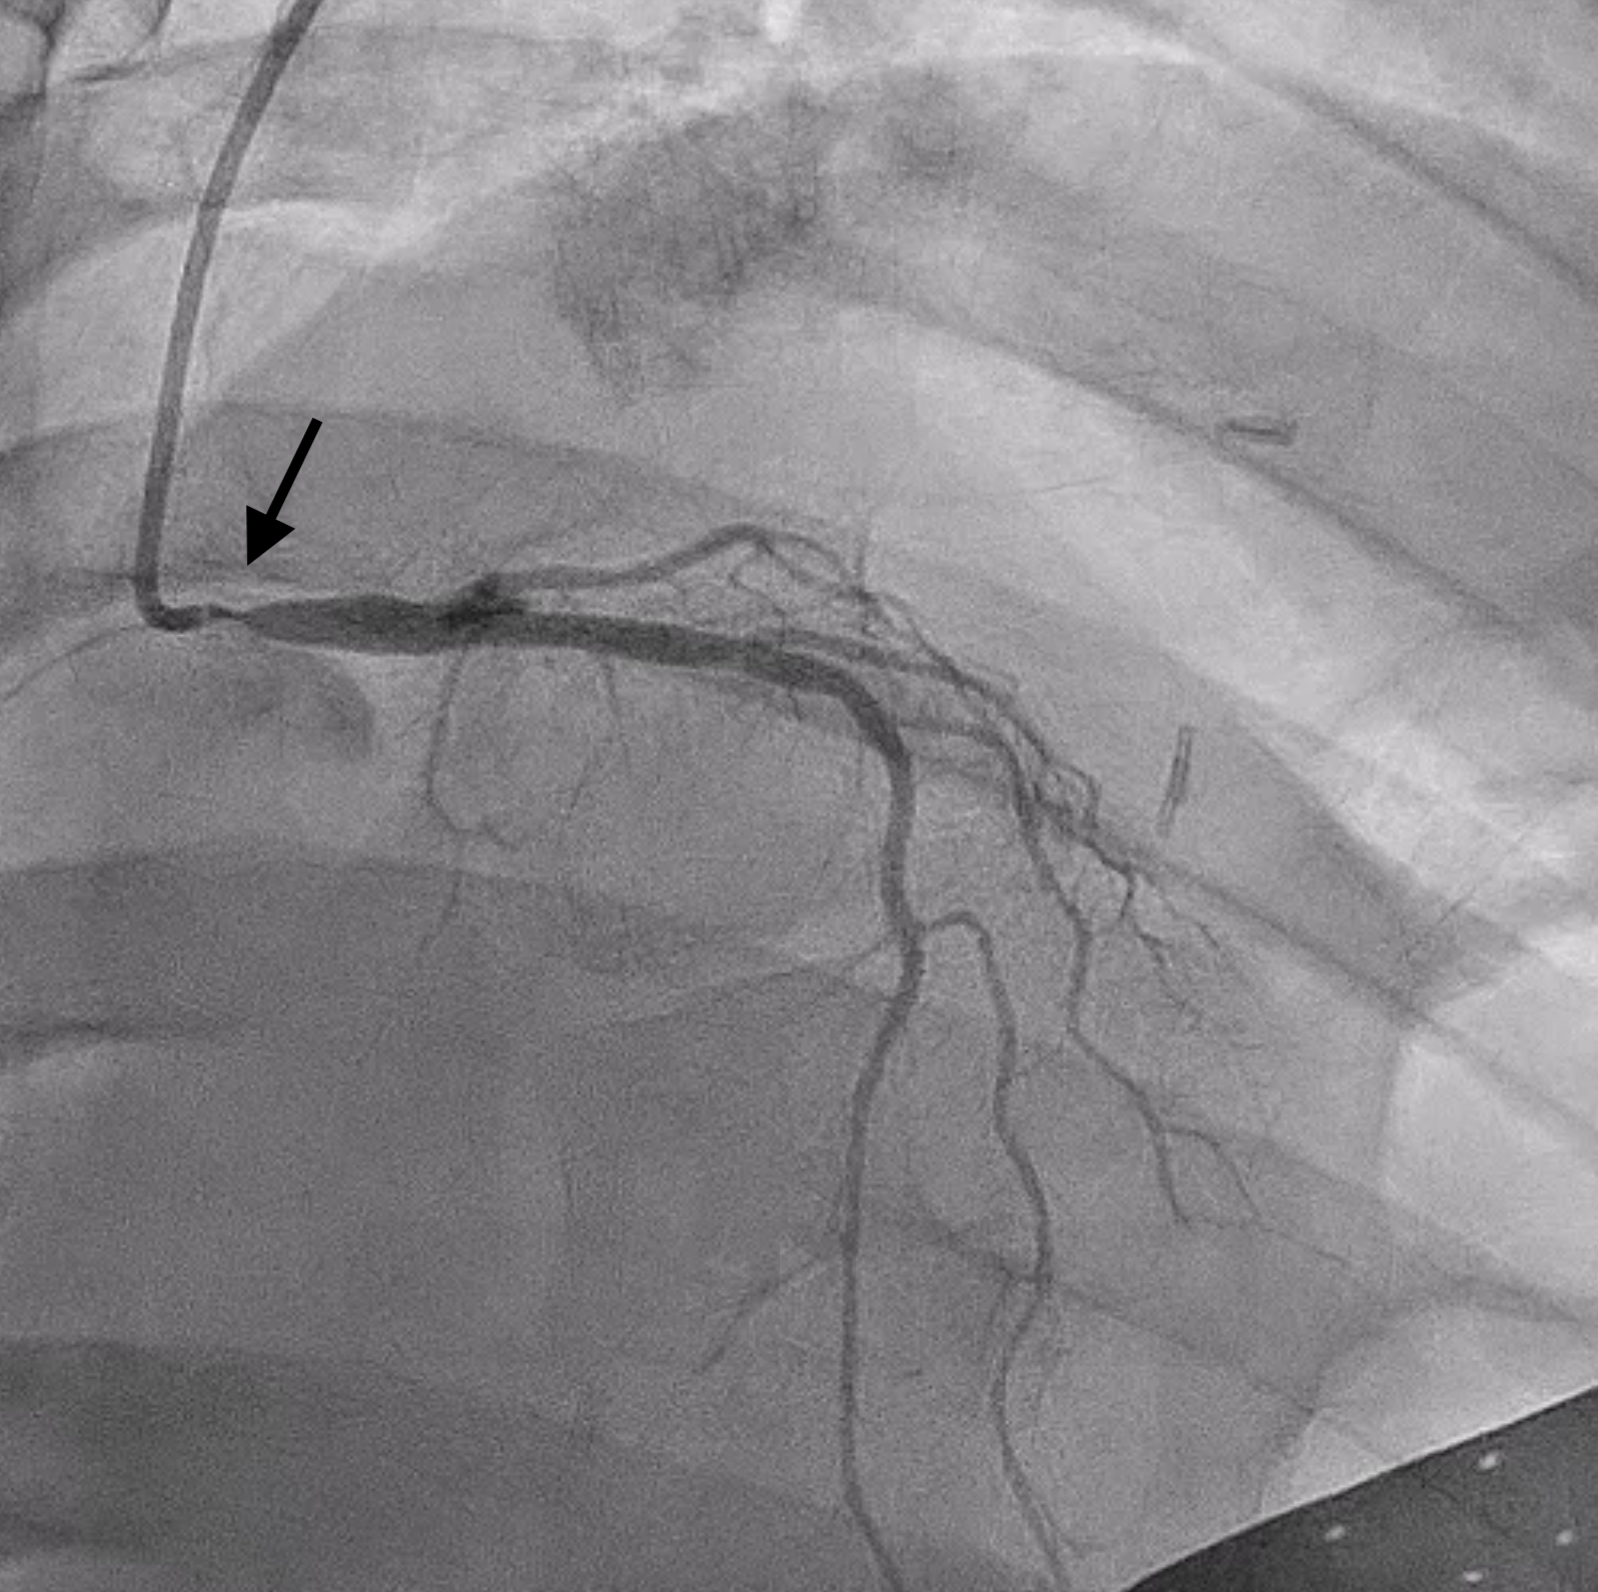

Left main has ostial to mid lesion with 90-95% stenosis. Left anterior descending and left circumflex and right coronary arteries have luminal irregularities without angiographic evidence of obstructive disease. Extreme angles were avoided during diagnostic angiogram in setting of her active pregnancy.

Patient had significant spasm of the bilateral radial arteries so right femoral artery access was obtained. A 6 Fr EBU 3.0 guide catheter was used to engage the left main coronary artery. A Sion wire was advanced into the LAD and a Sion Blue wire was advanced into the left circumflex. Pre-dilation was performed with a 2.5 x 12 mm semi-compliant balloon. IVUS showed MLA of 1.5 mm2 with intramural hematoma and evidence of plaque and thrombus. There was no evidence of SCAD on IVUS imaging. A 4 x 18 mm DES was placed in the left main and post-dilated with a 4.5 x 15 mm and 5 x 8 mm NC balloon. Final angiogram and IVUS confirmed excellent stent expansion/apposition with large MSA (11.8 mm2) and proximal stent edge in the ostium of the left main. Total air kerma was <500 mGy and and DAP was 50 Gy-cm2.